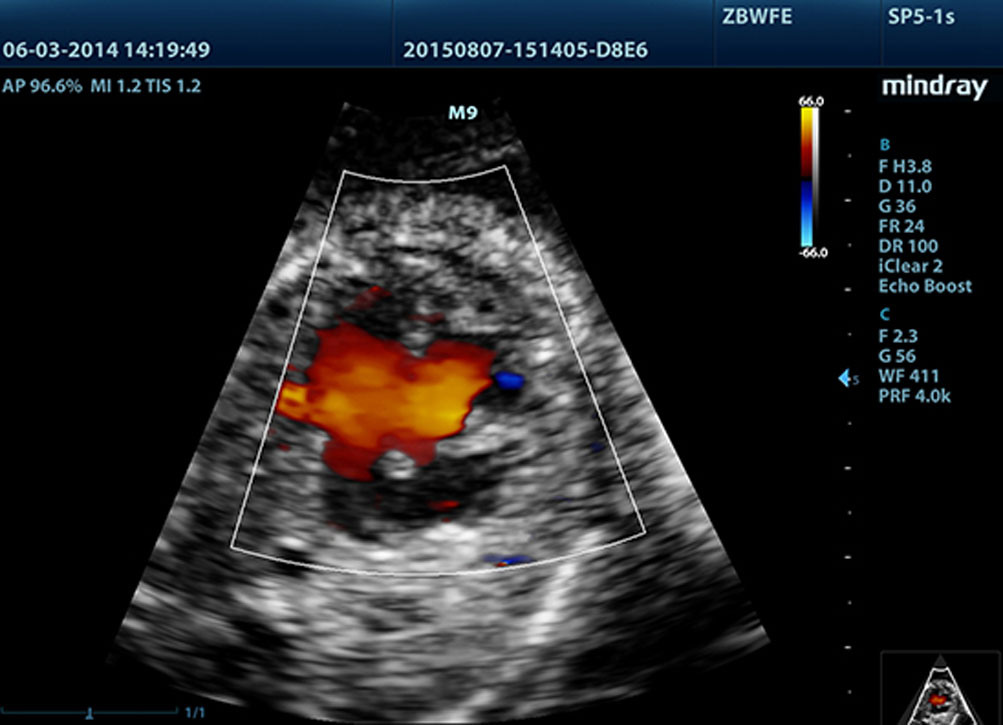

Stres Ekokardiyografili LVO

M9'un yĂŒksek kalitedeki becerileri stres s?ras?nda, endokardiyal yĂŒzeyin daha iyi g?rĂŒntĂŒlenmesini sa?layarak ve miyokardiyal doku ile kan havuzu aras?ndaki ayr?m? art?rarak LV i?in opasifikasyona izin verir M9'da bulunan Stres Eko ?zelli?i farmakolojik stres ve egzersiz stres ekosu i?in komple bir paket i?erir. Paket, bireysel ihtiya?lara g?re optimize edilebilen esnek bir raporlama sistemi taraf?ndan desteklenir.